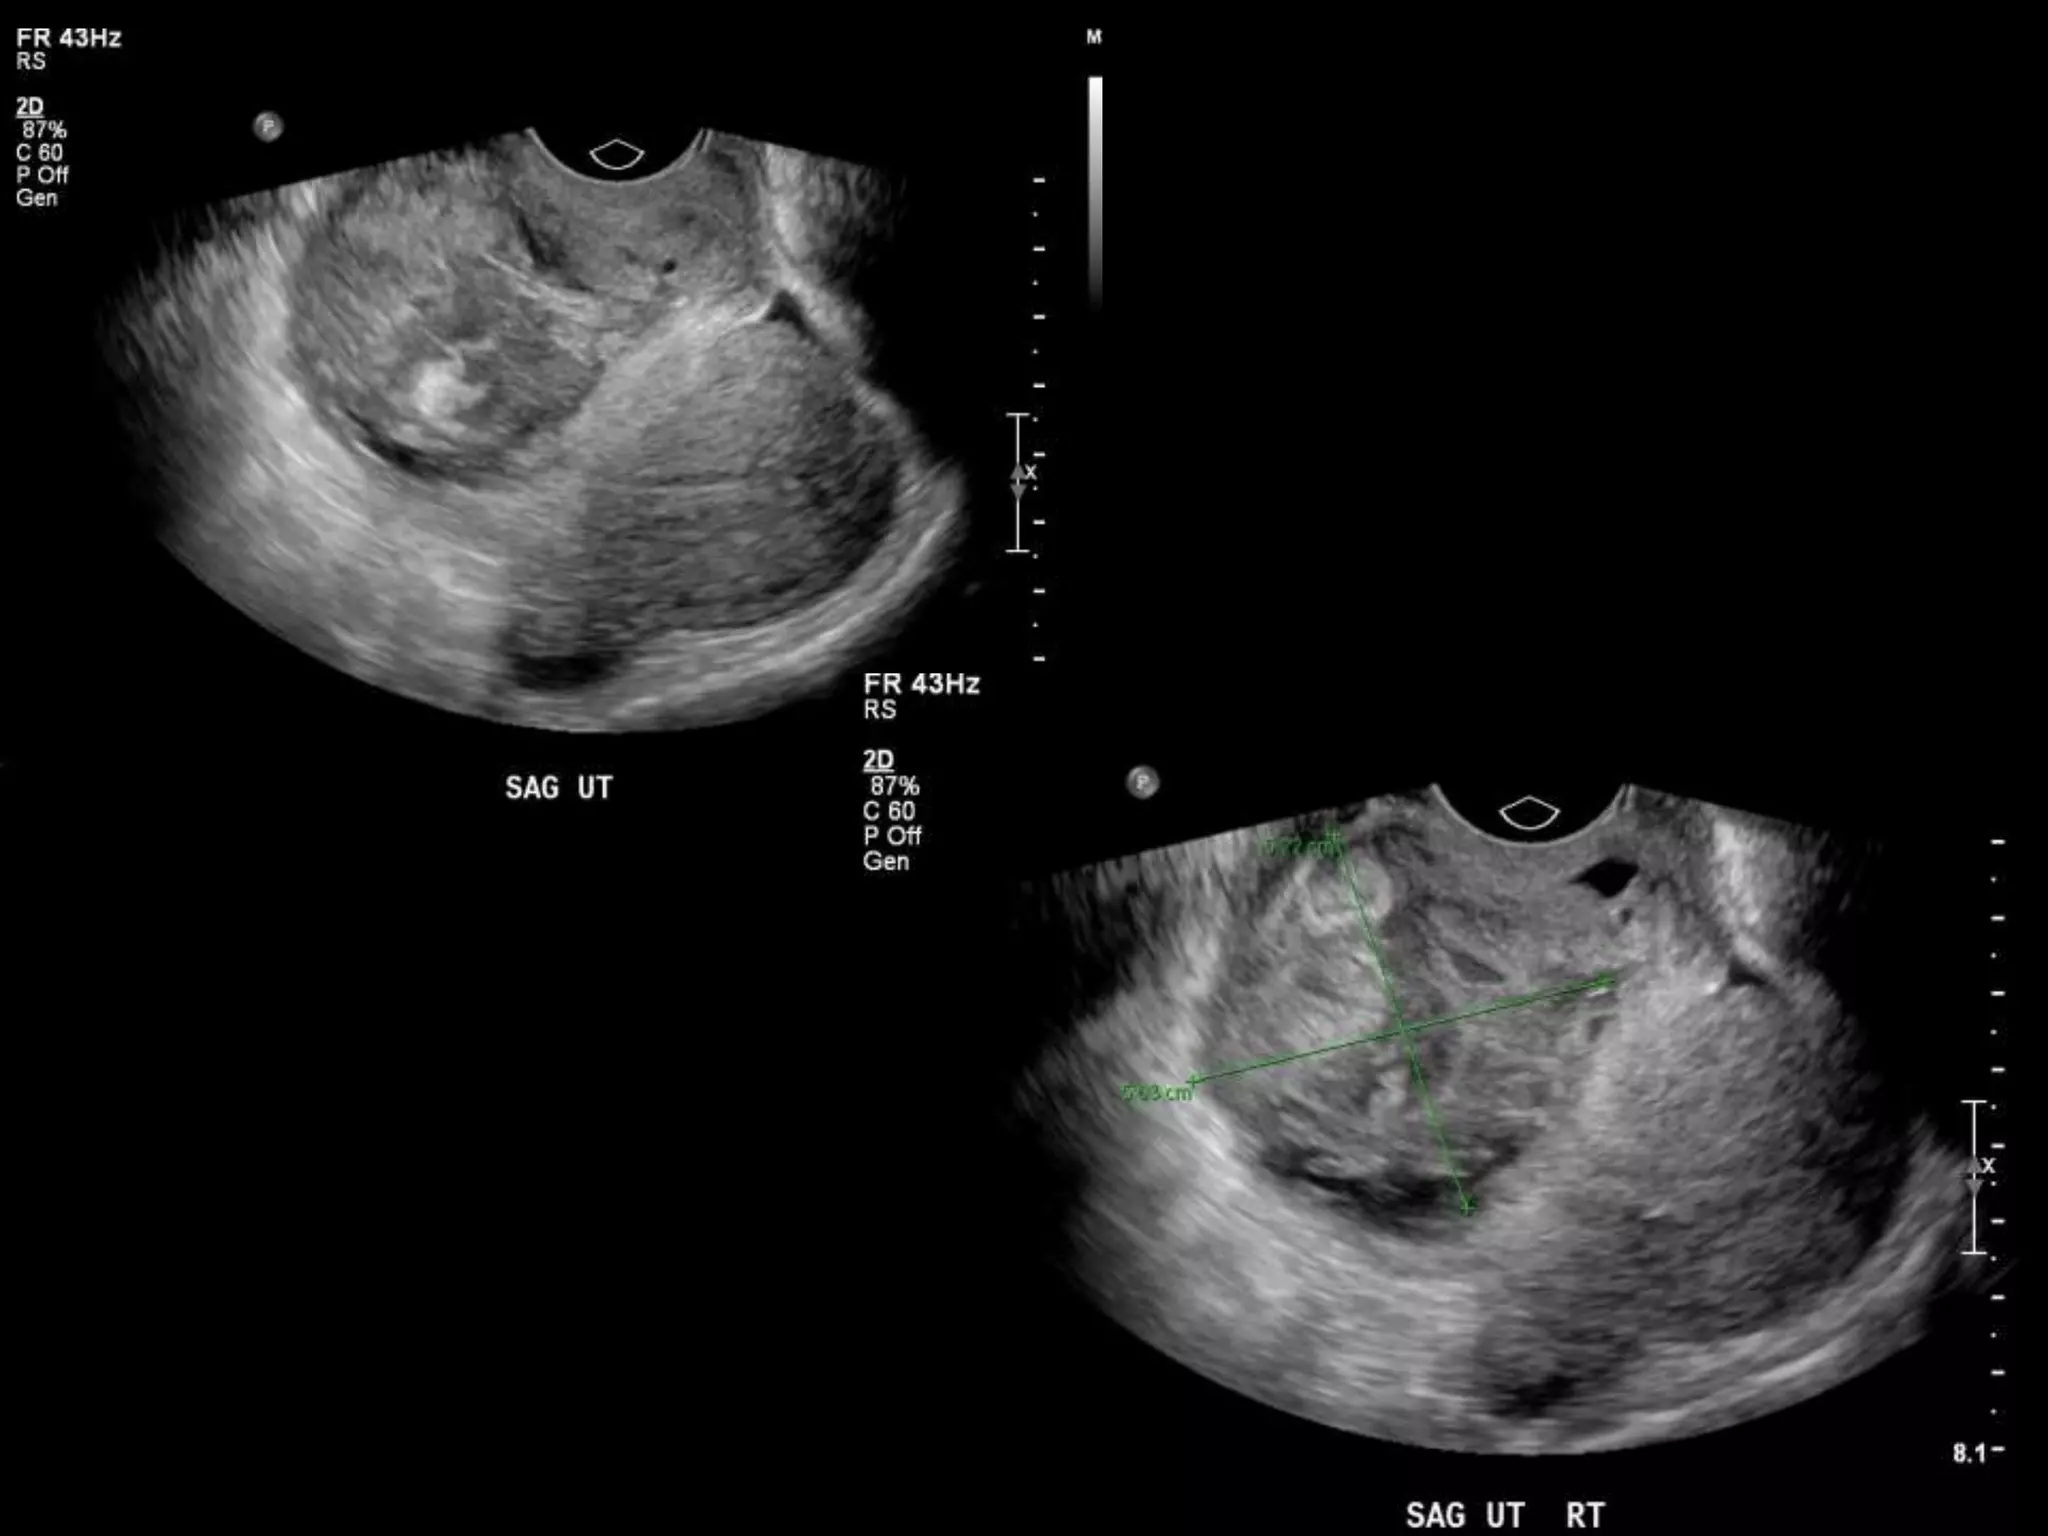

HISTORY

โ€ข 40 yo female 8.5 weeks pregant

โ€ข S/P D&C for pregnancy implanted at site of

c-section scar

โ€ข 6 weeks post D&C patient presents with

heavy persistent bleeding

โ€ข For Pelvic US

โ€ข HCG = 451 mIU/mL

HISTORY โ€ข 40 yofemale 8.5 weeks pregant โ€ข S/P D&C for pregnancy implanted at site of c-section scar

• 42.

โ€ข 6 weekspost D&C patient presents with heavy persistent bleeding โ€ข For Pelvic US โ€ข HCG = 451 mIU/mL

D&C complicated byPerforation, AVM w RPOC at Site of Perforation โ€ข AVM โ€“ Acquired or Congenital โ€ข Acquired โ€“ Traumatic โ€“ D&C, TAB, uterine surgery โ€“ Less common: Endometrial / Cervical CA, GTD โ€“ Clue on US: numerous tortuous vessels, high velocities โ€ข Tx: โ€“ transcatheter arterial embolization โ€ข Potential to preserve fertility โ€“ UA ligation, hysterectomy

POST PROCEDURE S/P embolizationof right UA and left UA due to cross collateralization

1 month followup HCG < 5 mIU/mL No flow in area โ€“ smaller in size Felt residual hematoma Will continue US follow up